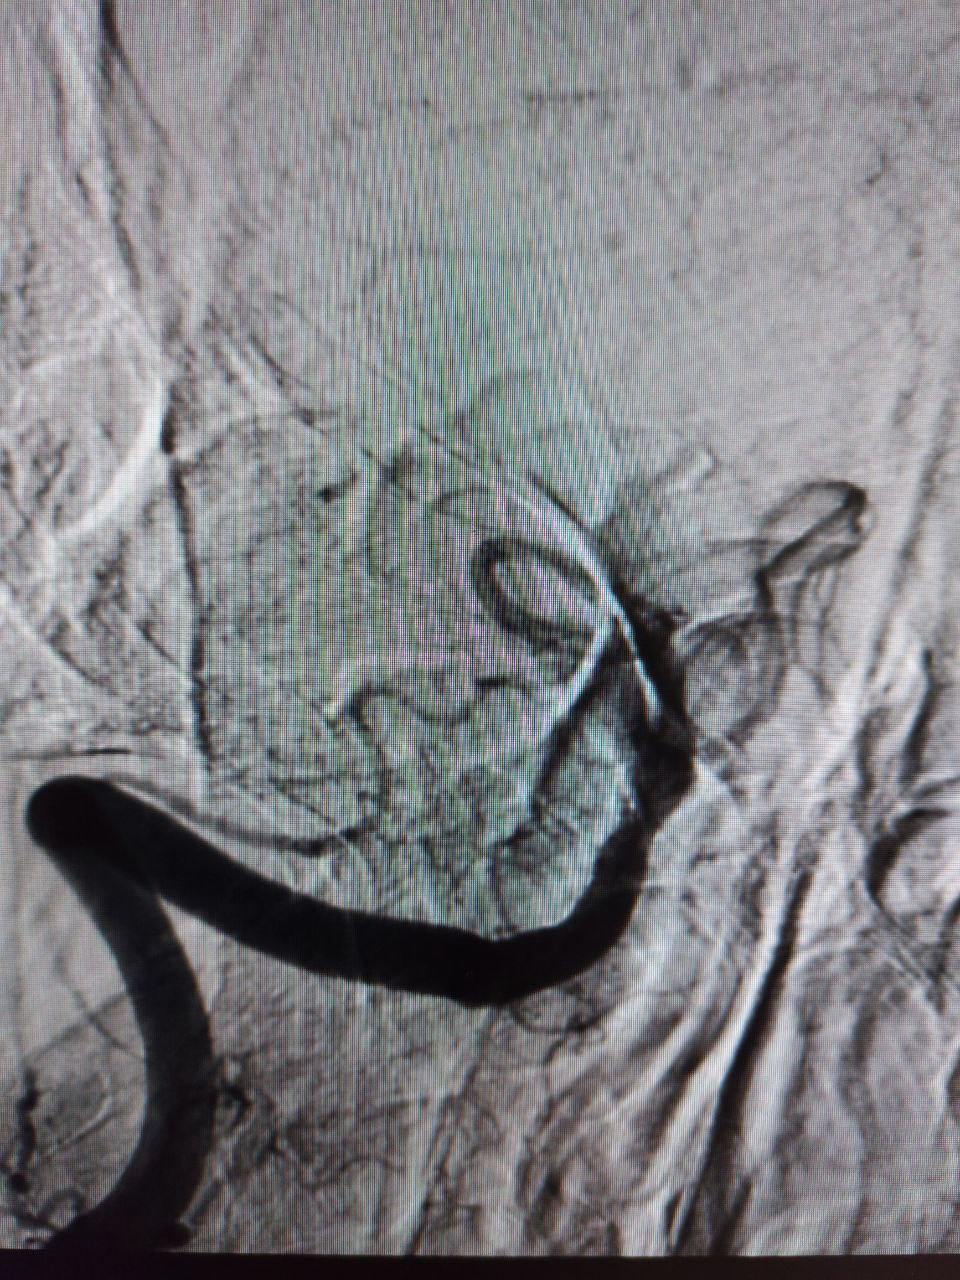

— У пациента был выявлен атеротромбоз — тромбоз на фоне атеросклеротической бляшки — основной артерии, которая обеспечивает кровоснабжение важнейших отделов головного мозга. Это очень тяжелое состояние с крайне высокой летальностью. Операция длилась около часа. После удаления тромба в артерии осталась бляшка, критически суживающая ее просвет: потребовалась имплантации стента. К счастью, мы успели вовремя, и операция прошла успешно, — прокомментировала заведующий центром Элеонора Тулякова.